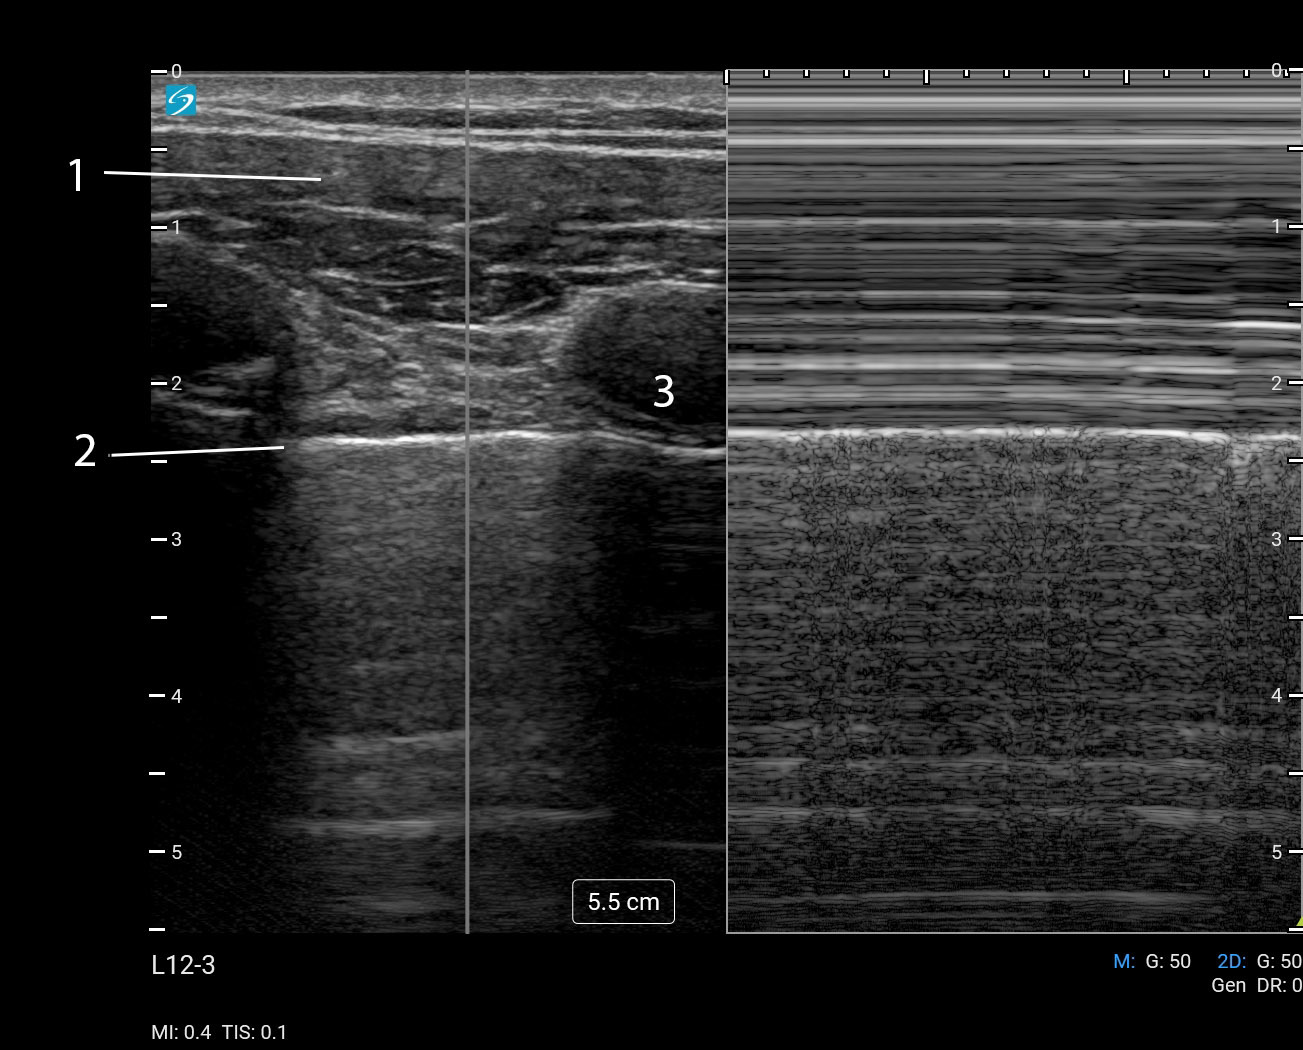

Lung M-Mode Linear (Sonosite PX L12-3) Image

Chest Wall

Pleural Interface

Rib